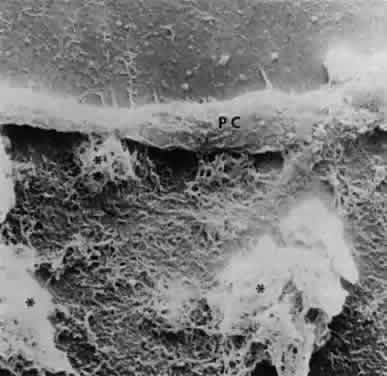

Accumulation of exfoliative material may be detected histopathologically throughout the anterior segment to include the lens, iris, trabecular structures, conjunctiva, ciliary body, and zonules. The deposition of fibrillar eosinophilic material on the anterior lens capsule is the classic histopathologic feature of XFS (Fig. 9). Ultrastructural studies also indicate some degree of actual exfoliative changes or peeling of the anterior lens capsule74 (Figs. 10 and 11). In addition, Ashton and associates describe a degenerative band containing exfoliative material within the inner half of the lens capsule.5 Bertelsen and coworkers independently noted projection of coarse fibrils from the lens surface into the deep portion of the lens capsule to form an amorphous layer of the lens capsule between the lens epithelium and normal lens capsule.6 Thus, studies indicate that exfoliative material accumulates on the anterior lens surface but also that the lens capsule itself may be involved, and that the underlying epithelial layer may at least partially contribute to the production of the exfoliative material.

Exfoliative material consists of an irregular meshwork of fibers composed of fibrillar subunits.74,92 Masses of these fibers correspond to the material seen clinically (see Fig. 10). The individual fibrils, which measure 6 to 8 nm in diameter and exhibit cross-banding at 10- to 12-nm intervals, are hypothesized to consist of macromolecules with a protein backbone and polysaccharide side chains.93–95 In contrast to collagen, the amino acid content of exfoliative material lacks hydroxyproline.96 Ringvold and Husby noted histochemical, immunologic, and ultrastructural features that led them to classify exfoliative material as an amyloid-like substance.97 Repo and associates note Congo red-positive staining for amyloid in the vessel walls of 7 of 13 iris specimens from exfoliation patients and believe that these findings support the theory that XFS is associated with amyloid.59 Immunohistochemical studies by other investigators show heparin sulfate and chondroitin sulfate proteoglycans, laminin, entactin/nidogen, fibronectin, and amyloid P protein to be components of exfoliation material.98,99 Schlötzer-Schrehardt and coworkers suggest that the material may be an expression of a disordered extracellular matrix synthesis.98